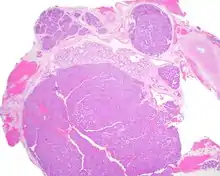

Most patients present in the 7th decade of life, with females affected much more commonly than males (about a 4:1 ratio). The vast majority of the tumors present in the upper lip, although a few present in the palate or buccal (cheek) tissue as a slowly enlarging mass.[3] It is curious that the tumor may show multifocality or multinodularity, a finding that should not be confused with invasion clinically or with malignancy.[1][4]

Tumors are usually small because they come to clinical attention early on in development, with an average size of about 1.6 cm.[1] There is a very characteristic appearance to the tumor when reviewed histologically.

There are often small luminal squamous balls or morules. There is a very well-developed supporting tissue that is a loose, fibrillar stroma, rich in hyaluronic acid and chondroitin sulphate.[1] In a few cases small calcifications or microliths may be present. Although seldom necessary, a pathologist can do immunohistochemistry studies to confirm the diagnosis, with the cells strongly reactive with pancytokeratin, S100 protein and SOX10, with a delicate GFAP reaction around the periphery.[5][1][6][7] Even though it is a benign tumor, it must be separated from a basal cell adenoma, pleomorphic adenoma, adenoid cystic carcinoma, and polymorphous adenocarcinoma.